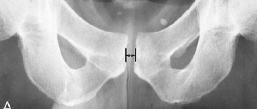

Q what is the name of this measurement? and what is the average + range?

A: Symphysis Pubis Width

assesses the width of the symphysis pubis joint. The average is 6 mm for males (range 4.8-7.2 mm) and 5 mm for females (range 3.8-6.0 mm).